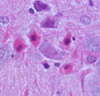

What is a gemistocyte?

***KNOW THIS***

Swollen astrocytes- cytoplasm contains pink “glassy” material